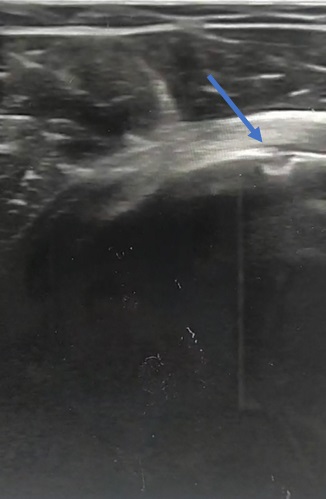

• Se realizó una ecografía, en la que se apreció una solución de continuidad en la cortical del húmero que hizo pensar en una avulsión del tendón del músculo subescapular.

• Juicio clínico: avulsión del tendón del músculo subescapular del hombro derecho.

En este caso la ecografía disminuyó la incertidumbre y permitió una mejor aproximación diagnóstica desde la primera valoración del paciente con una pequeña inversión de tiempo durante la consulta.